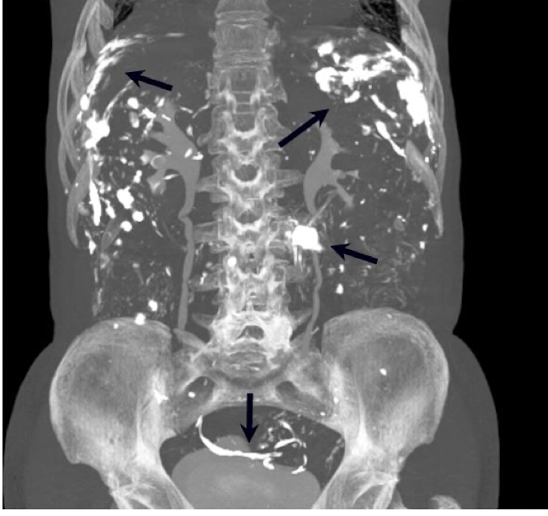

What is this and what type of scan

Polycystic kidney disease, CT scan